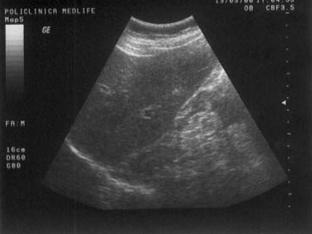

Figura

14. Mas[ gigant[ care ocup[ micul bazin =i abdomenul mediu, de aproximativ

30 cm diametru, cu structur[ complex[ 80% lichidian[, restul solid[. Partea

solid[ este dispus[ sub form[ de septuri. Aspectul sugereaz[ histademom cu

apartenen[ ovarian[.